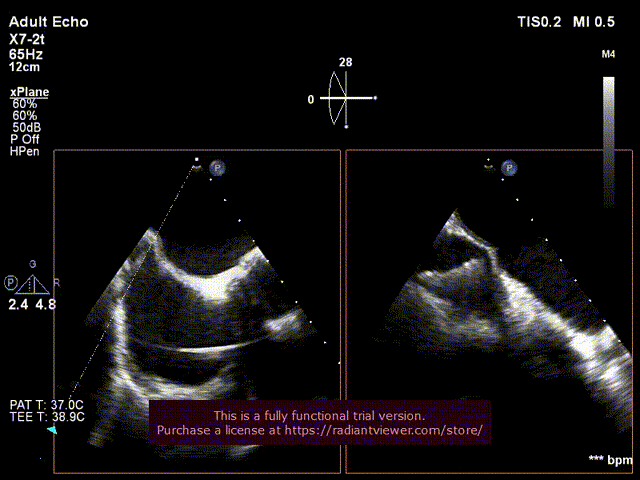

TAVR+TMVR一站式操作全过程:(食道超声与术中造影相结合)

6.经食道超声评估主动脉瓣位SAPIEN 3植入

位置良好,瓣叶运动良好,无反流